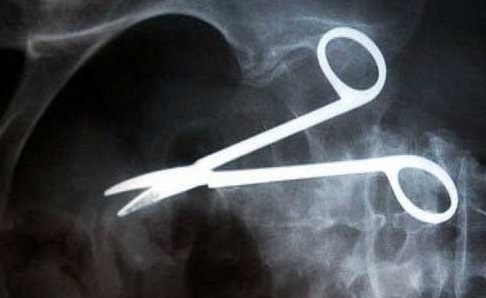

مقص ″يرقد″ اثنا عشرا عاما في جسم مريض

خضع مواطن كازاخستاني الى عملية جراحية كبيرة ناجحة قبل 12 سنة، ولكنه خلال هذه الفترة كان يشعر بألم شديد ومستمر كلما تناول الطعام. وتبين ان سبب هذه الألم هو المقص الذي نساه الجراحون داخل جسمه خلال العملية الجراحية التي خضع لها قبل 12 سنة في احد مستشفيات كازاخستان. فقبل فترة قصيرة فقد هذا الشخص "53 سنة" الشهية تماما من جراء الألم وبدأ جسمه بالنحول، فقرر اجراء الفحوصات اللازمة لتشخيص السبب. من ضمن الفحوصات الطبية التي اجريت له كان التصوير بالأشعة السينية التي بينت وجود مقص طوله 20 سم في بطنه. ويقول احد الأطباء، "يبدو ان الجراح الذي اجرى العملية للمريض نسي المقص في بطنه، ويمكنني تصور الآلام التي كان هذا المريض يشعر بها طوال هذه الفترة". وبعد اجراء التحقيق تبين ان الجراح المذكور توفي قبل ثلاث سنوات. ومن جانبه اعلن المريض انه لا ينوي تقديم شكوى ضد أحد، ولكنه يطلب اجراء عملية فورية لإخراج المقص من بطنه وهذا ما حصل فعلا.